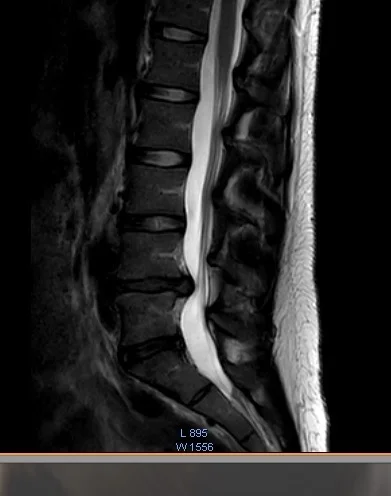

Vaivaksi jäi puutunut ja heikko jalka. Reisi hieman puutunut, pohje ja jalan ulkosyrjä sekä ulommat varpaat puutuneimmat. Kävin itse MRIssä kun ei lähetettä saanut. Pullistuma painaa (L5) S1 juuren tyvialuetta.